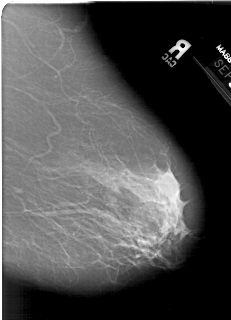

A_1386_1.RIGHT_CC

RIGHT_CC LINES 6826 PIXELS_PER_LINE 4006 BITS_PER_PIXEL 12 RESOLUTION 43.5 NON_OVERLAY